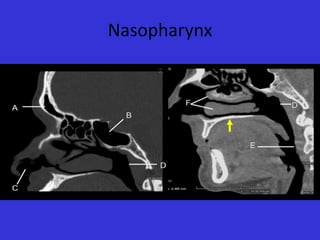

Nasopharynx

A.

B.

C.

D.

E.

F.

Frontal Sinus

Sphenoid Sinus

Nostril

Posterior Nasopharyngeal wall

Posterior esophageal wall

Nasal turbinate

Para Nasal Sinuses A. B. C. D. E. F. FrontalSinus Sphenoid Sinus Nostril Posterior Nasopharyngeal wall Posterior esophageal wall Nasal turbinate